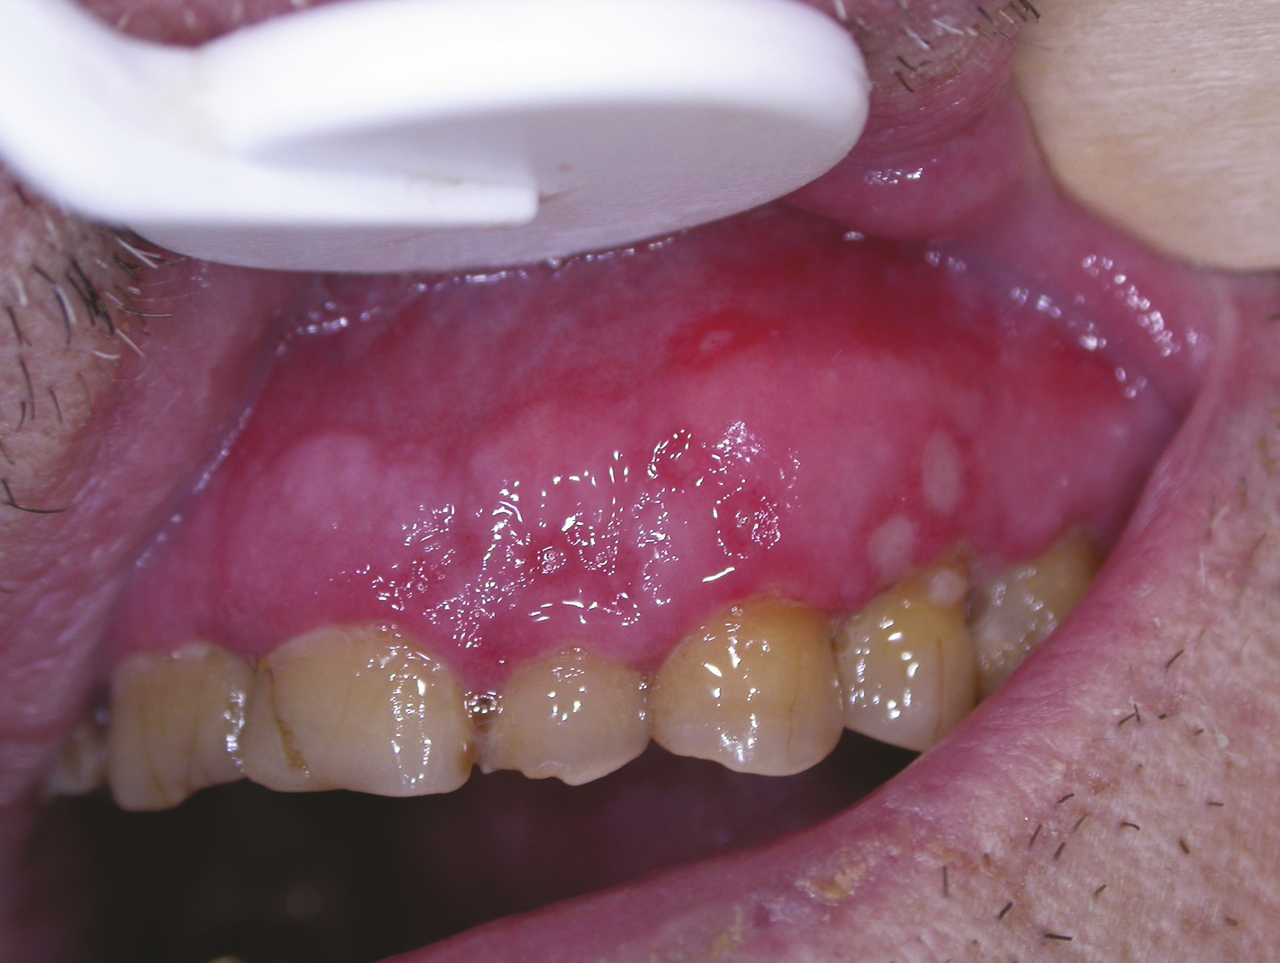

La primo-infection herpétique se traduit par une gingivostomatite aiguë survenant souvent pendant la petite enfance, mais elle n’est pas rare chez l’adolescent ou l’adulte jeune. Elle débute par de la fièvre, un malaise général, des douleurs pharyngées et gingivales ; des vésicules multiples parfois confluentes et polycycliques apparaissent sur une muqueuse érythémateuse. L’atteinte gingivale est constante (fig. 5) associée à des adénopathies cervicales sensibles. La guérison est spontanée en 2 à 3 semaines.